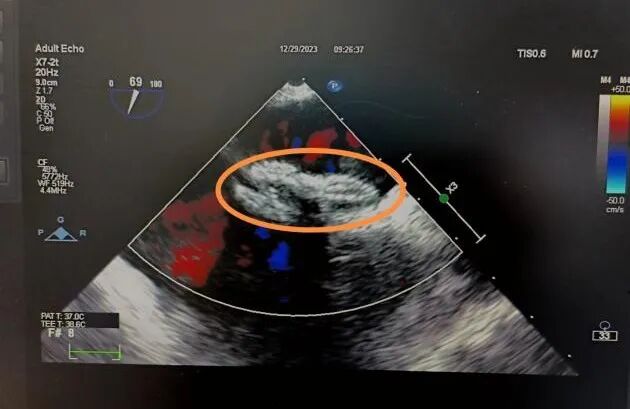

手术于纯超声引导下开展,心外科团队在超声科郇致福高级医生及麻醉科王小雷顾问医生精密配合操作下,顺利将一枚可降解封堵器植入李女士心脏卵圆孔未闭处,展开双盘面、锁定、释放封堵器,顺利完成封堵。

术后超声复查显示,封堵器成型稳定,双盘牢牢贴附房间隔,形态位置良好,无残余分流,封堵效果非常理想,手术顺利成功。